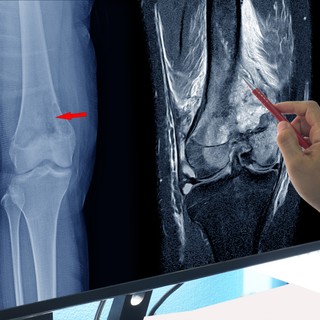

Az oszteoszarkóma kimutatására egyszerű hagyományos röntgenfelvétel is elegendő a rendkívül jellegzetes kép alapján. Így műtét előtti kimetszésből végzett szövettani vizsgálatnak nincs sok értelme, azzal csak a fertőzéses és vérzéses szövődmények gyakorisága növekszik.

A betegség szóródásának feltérképezésére nagy felbontóképességű radiológiai eljárásokat alkalmaznak (CT, MRI, PET). Különösen a sugárterheléssel nem járó MRI alkalmas a csontáttétek gyógyulásának nyomon követésére.